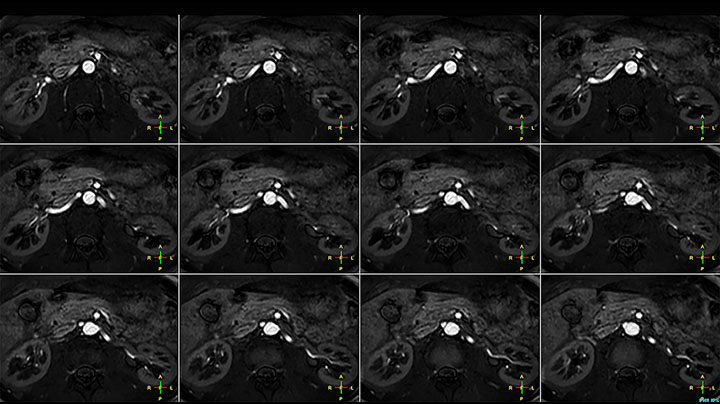

This patient is a 43-year-old female with a left supraclavicular nerve sheath tumor. The lesion is well visualized on the STIR VISTA images and on the MR neurography using DWIBS. The exam was performed on Prodiva 1.5T.

Acq voxel size 1.2 x 1.3 x 2.4 mm, Recon voxel size 0.7 x 0.7 x 1.2 mm, dS SENSE factor 2, scan time 5:46 min.